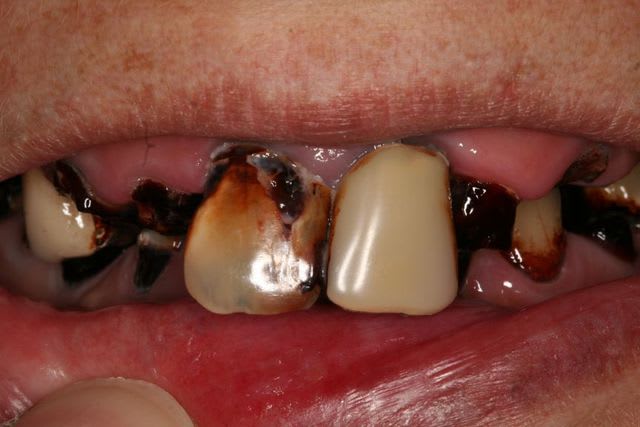

fouilla

est venu nous voir uniquement parce que le scellement (quatre fois en un an) de 21 ne tenait pas pour qu'on lui rescelle définitivement...

un peu de colle et hop